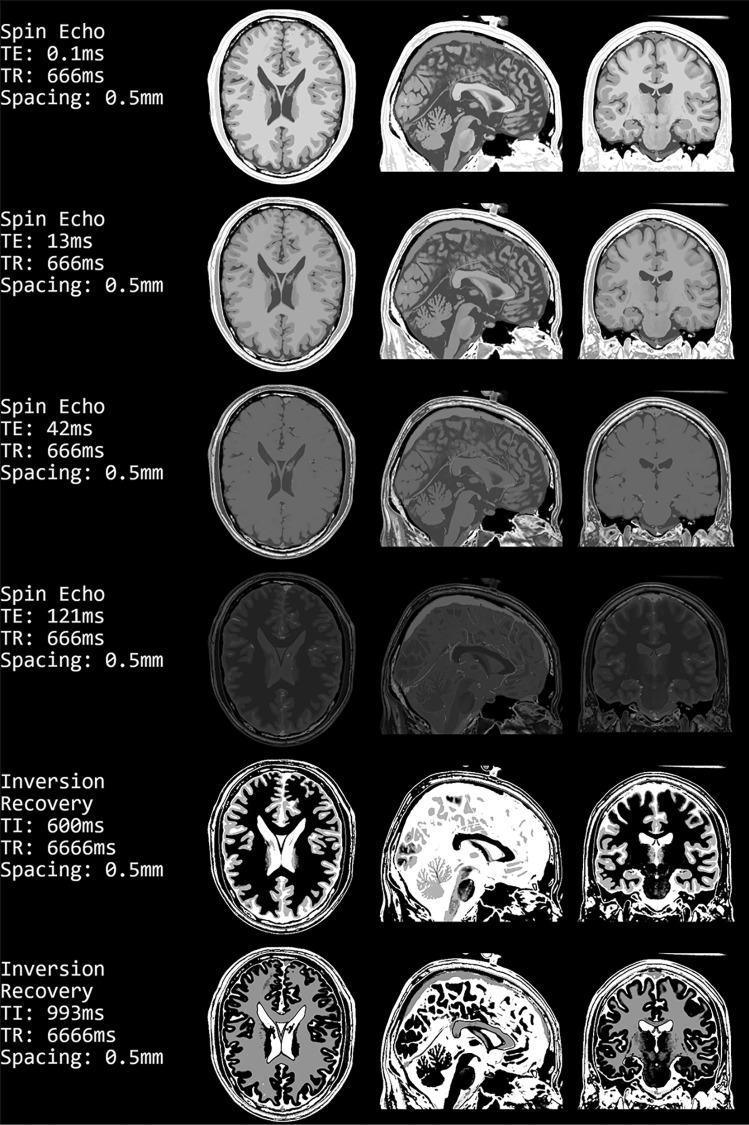

Magnetic resonance image formation is not trivial and remains a difficult subject for teaching. Therefore, we saw an urgent need to facilitate teaching by developing a practical and easily accessible MR image generator. Due to the increasing interest in X-nuclei MRI, sodium image generation is also offered. The tool is implemented as a web application that is compatible with all standard desktop browsers and is open source. The user interface focuses on the parameters needed for the creation and display of the resulting images. Available MR sequences range from the standard Spin Echo and Inversion Recovery over steady-state to conventional sodium and more advanced single and triple quantum sequences. Additionally, the user interface has parameters to alter the resolution, the noise, and the k-space sampling. Our software is free to use and specifically suited for teaching purposes.

磁共振成像是一项不简单的任务,并且仍然是一个难以教授的主题。因此,我们认为有必要通过开发一个实用且易于访问的磁共振图像生成器来促进教学。由于对 X 核 MRI 的兴趣日益增加,我们还提供了钠图像生成功能。该工具作为一个网络应用程序实现,与所有标准桌面浏览器兼容,并且是开源的。用户界面侧重于创建和显示结果图像所需的参数。可用的磁共振序列范围从标准的自旋回波和反转恢复到稳态,再到常规的钠和更先进的单量子和三量子序列。此外,用户界面还有用于改变分辨率、噪声和 k 空间采样的参数。我们的软件是免费使用的,特别适合教学用途。